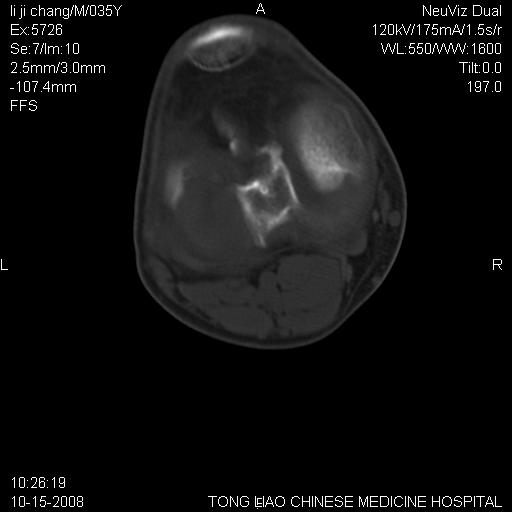

男,35岁,骨科诊断骨性关节炎。继往使用过激素,现股骨头坏死。膝关节病变,请会诊

一元论-----亦考虑为坏死

支持考虑无菌坏死

支持无菌坏死伴退行性骨关节病.

剥脱性骨软骨炎:是一种关节下软骨及软骨下骨缺血性坏死。

支持 无菌性坏死伴退行性骨关节病。